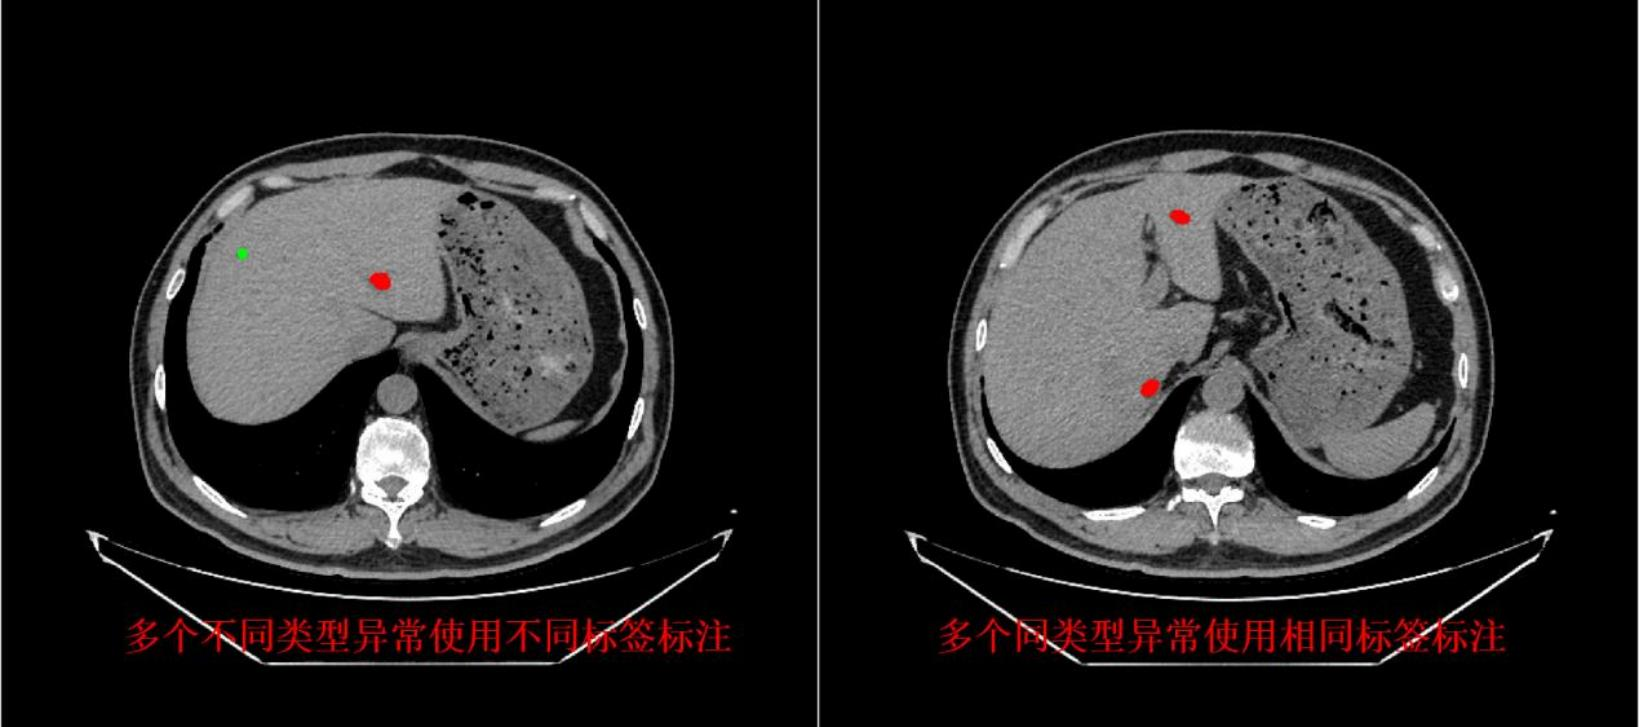

长沙朗慧信息科技有限公司是一家专注于数据标注服务的创新型企业,秉持 “数据驱动,智能创新” 理念,依托人工智能技术和大数据分析,提供高质量、准确、高效的数据标注解决方案。其服务聚焦医疗数据领域,涵盖医学影像、医疗文本及多模态数据融合标注等,通过智能辅助标注、多轮交叉校验等方式保障质量与效率,旨在以数据标注为切入点,助力释放医疗数据价值,推动医疗健康行业智能化发展,用科技改变医疗数据的未来。